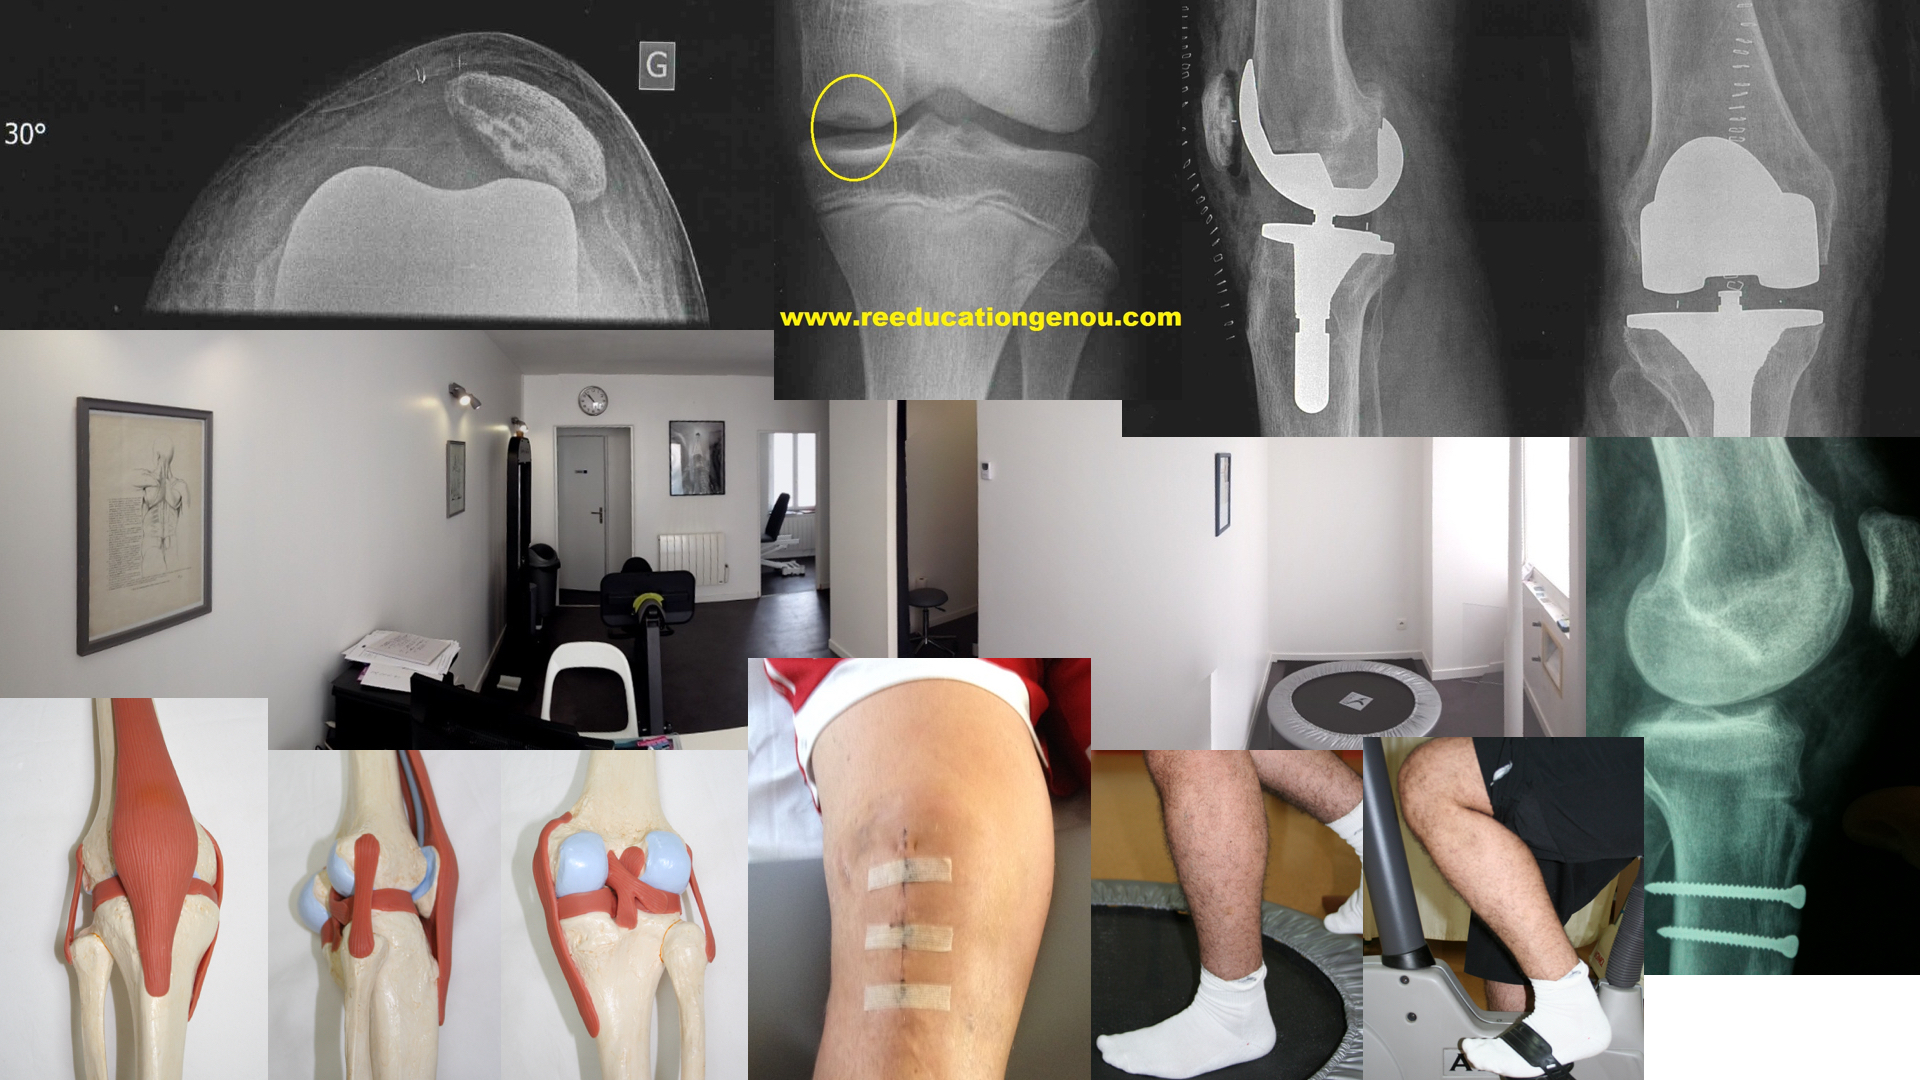

Reeducationgenou Com Le Ligament Croise Anterieur

visitez l'article complet ici : https://www.reeducationgenou.com/les-ligaments/le-ligament-crois%C3%A9-ant%C3%A9rieur/